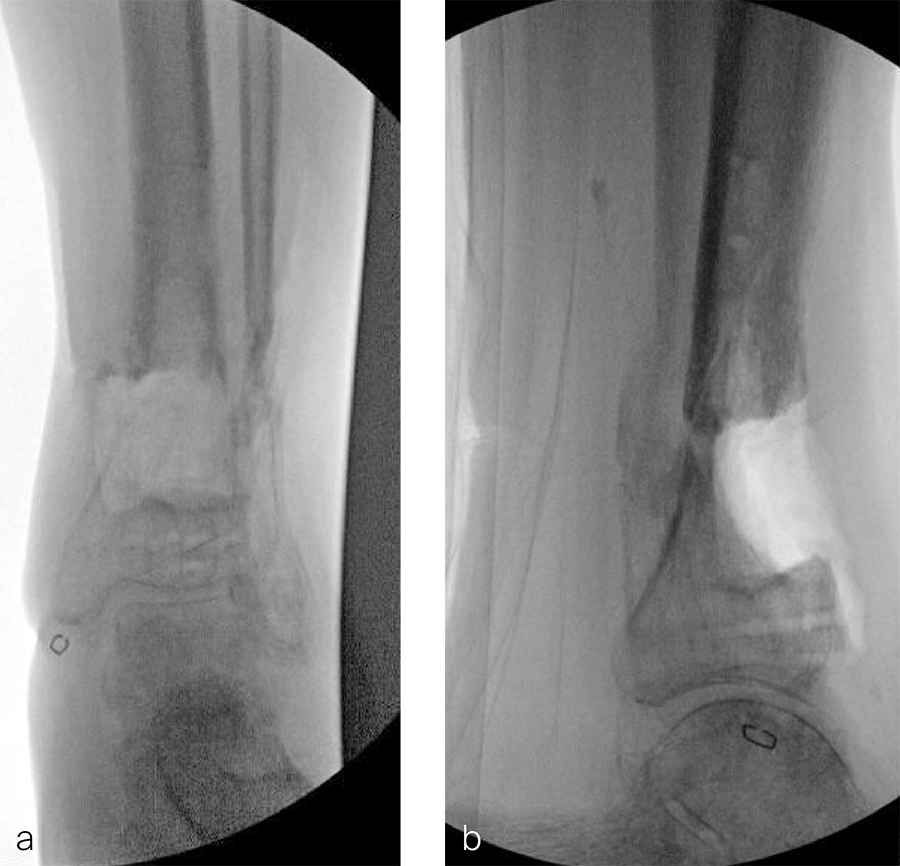

The patient was discharged on hospital day 6 to a rehabilitation facility with his left lower extremity in a splint and touch down weight bear allowance. He returned 2 weeks later with drainage from the medial traumatic wound. In addition, he had a gastrointestinal bleed from use of nonsteroidal antiinflammatory drugs. Once the gastrointestinal bleed was stabilized, he was taken the next day to the OR for another incision and drainage. Further, more significant, devitalized bone was resected, and an antibiotic cement spacer was placed (Fig 3). Deep culture samples were taken despite knowing the antibiotic resorbable beads had been placed in the wound at the time of initial closure. The plate was left in place, but a planned exchange plate/nailing was to be performed pending final culture results.

Cultures eventually yielded Klebsiella pneumoniae and Enterobacter cloacae. The patient was administered intravenous antibiotics for 6 weeks and was discharged home with therapy and nursing. He returned to the clinic with wound breakdown and an exposed cement spacer at 10 weeks after injury. Further bone debridement, spacer exchange, repeated culture samples, and plastic surgery were undertaken to help with wound coverage with a rotational flap. The microbiological culture was still positive for Klebsiella pneumoniae.

Two months later, the patient had a staged cement spacer removal and hardware removal followed by a new spacer placement (Fig 4). When microbiological cultures were negative for 5 days he was taken to the OR for definitive fixation and bone grafting. RIA bone graft from the ipsilateral femur was taken, a new anterior lateral plate was placed with an adjunct IM nail (and angle stable screws) as the distal plafond was now one articular block (Fig 5).